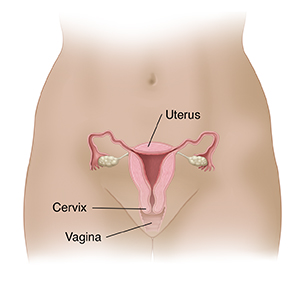

The role of the cervix

The cervix is circular. It connects the uterus to your vagina and provides a passage for menstrual blood and sperm. During pregnancy, it helps hold the fetus inside your uterus. During birth, the baby passes through the cervix during childbirth.